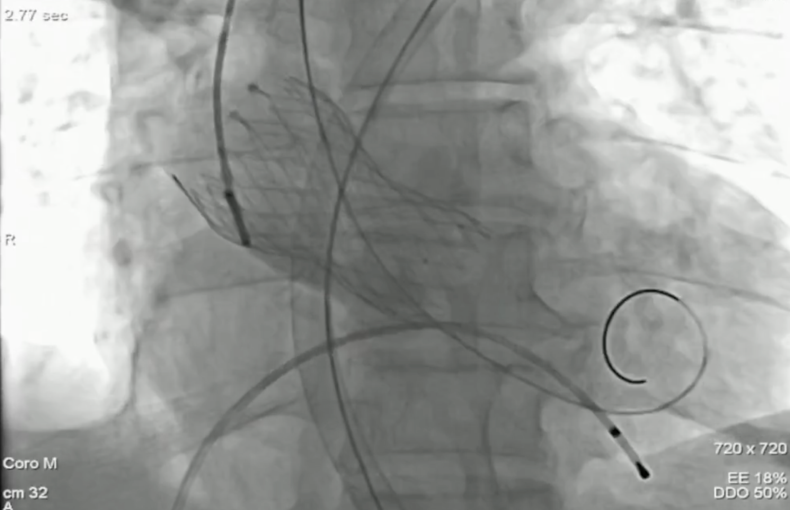

手术中经右股动脉入路,拟植入VenusA-L 29mm瓣膜。因弓部角度锐利,导丝跨弓两次尝试后成功,造影未见主动脉夹层。最终在超声引导下回收重置,瓣膜同轴性理想,展开良好,反流完全消失,手术顺利完成。

瓣膜过弓

瓣膜释放